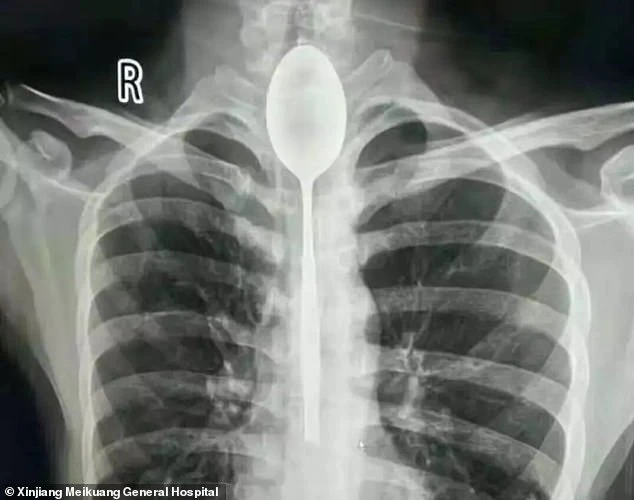

Phim chụp X-quang cho thấy chiếc thìa trong thực quản. Ảnh: Bệnh viện đa khoa Meikuang

Mắc kẹt thìa dài 20 cm trong thực quản suốt 1 năm

(PLO)- Chiếc thìa nằm yên trong thực quản người đàn ông suốt một năm cho đến ngày ông bị đấm vào ngực.

Một người đàn ông Trung Quốc đã lỡ nuốt một chiếc thìa kim loại dài 20 cm sau một trò cá cược ngu ngốc lúc say xỉn. Tuy nhiên, sau đó ông này thấy mình vẫn có thể ăn uống bình thường nên cũng chẳng thèm đến bệnh viện để lấy nó ra.

Người đàn ông giấu tên sống ở Tân Cương, Trung Quốc nói với các bác sĩ rằng ông đã nuốt cái thìa này khoảng một năm trước. Lúc đó, ông nói với bạn bè rằng ông có thể nuốt chiếc thìa và sau đó kéo nó trở lại bằng một sợi dây. Tuy nhiên, "màn xiếc" thất bại và ông ta sống chung với chiếc thìa trong thực quản một năm nay.

Cái thìa có lẽ vẫn còn bị mắc kẹt trong thực quản của ông lâu hơn nếu ông không bị đấm vào ngực. Cú đấm khiến ông ta đau ngực và khó thở. Lúc này, ông ta mới chịu đến Bệnh viện đa khoa Meikuang Tân Cương để kiểm tra.

Sau khi thảo luận, các bác sĩ tại Bệnh viện đa khoa Meikuang Tân Cương quyết định nội soi để lấy chiếc thìa ra. Ca phẫu thuật thành công và hiện người đàn ông đang hồi phục tốt và sẽ sớm được xuất viện.